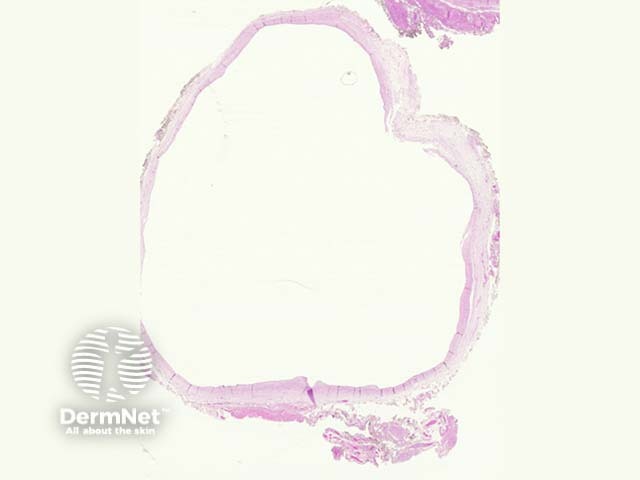

These are lined by urothelium, cuboidal, flat or atrophic epithelia (figures 1, 2, 3). The cyst may be located at any point between the bladder and the umbilicus. The surrounding dermis or soft tissue often shows fibrosis, calcification and reactive changes (figures 1, 2, 3)

Figure 1